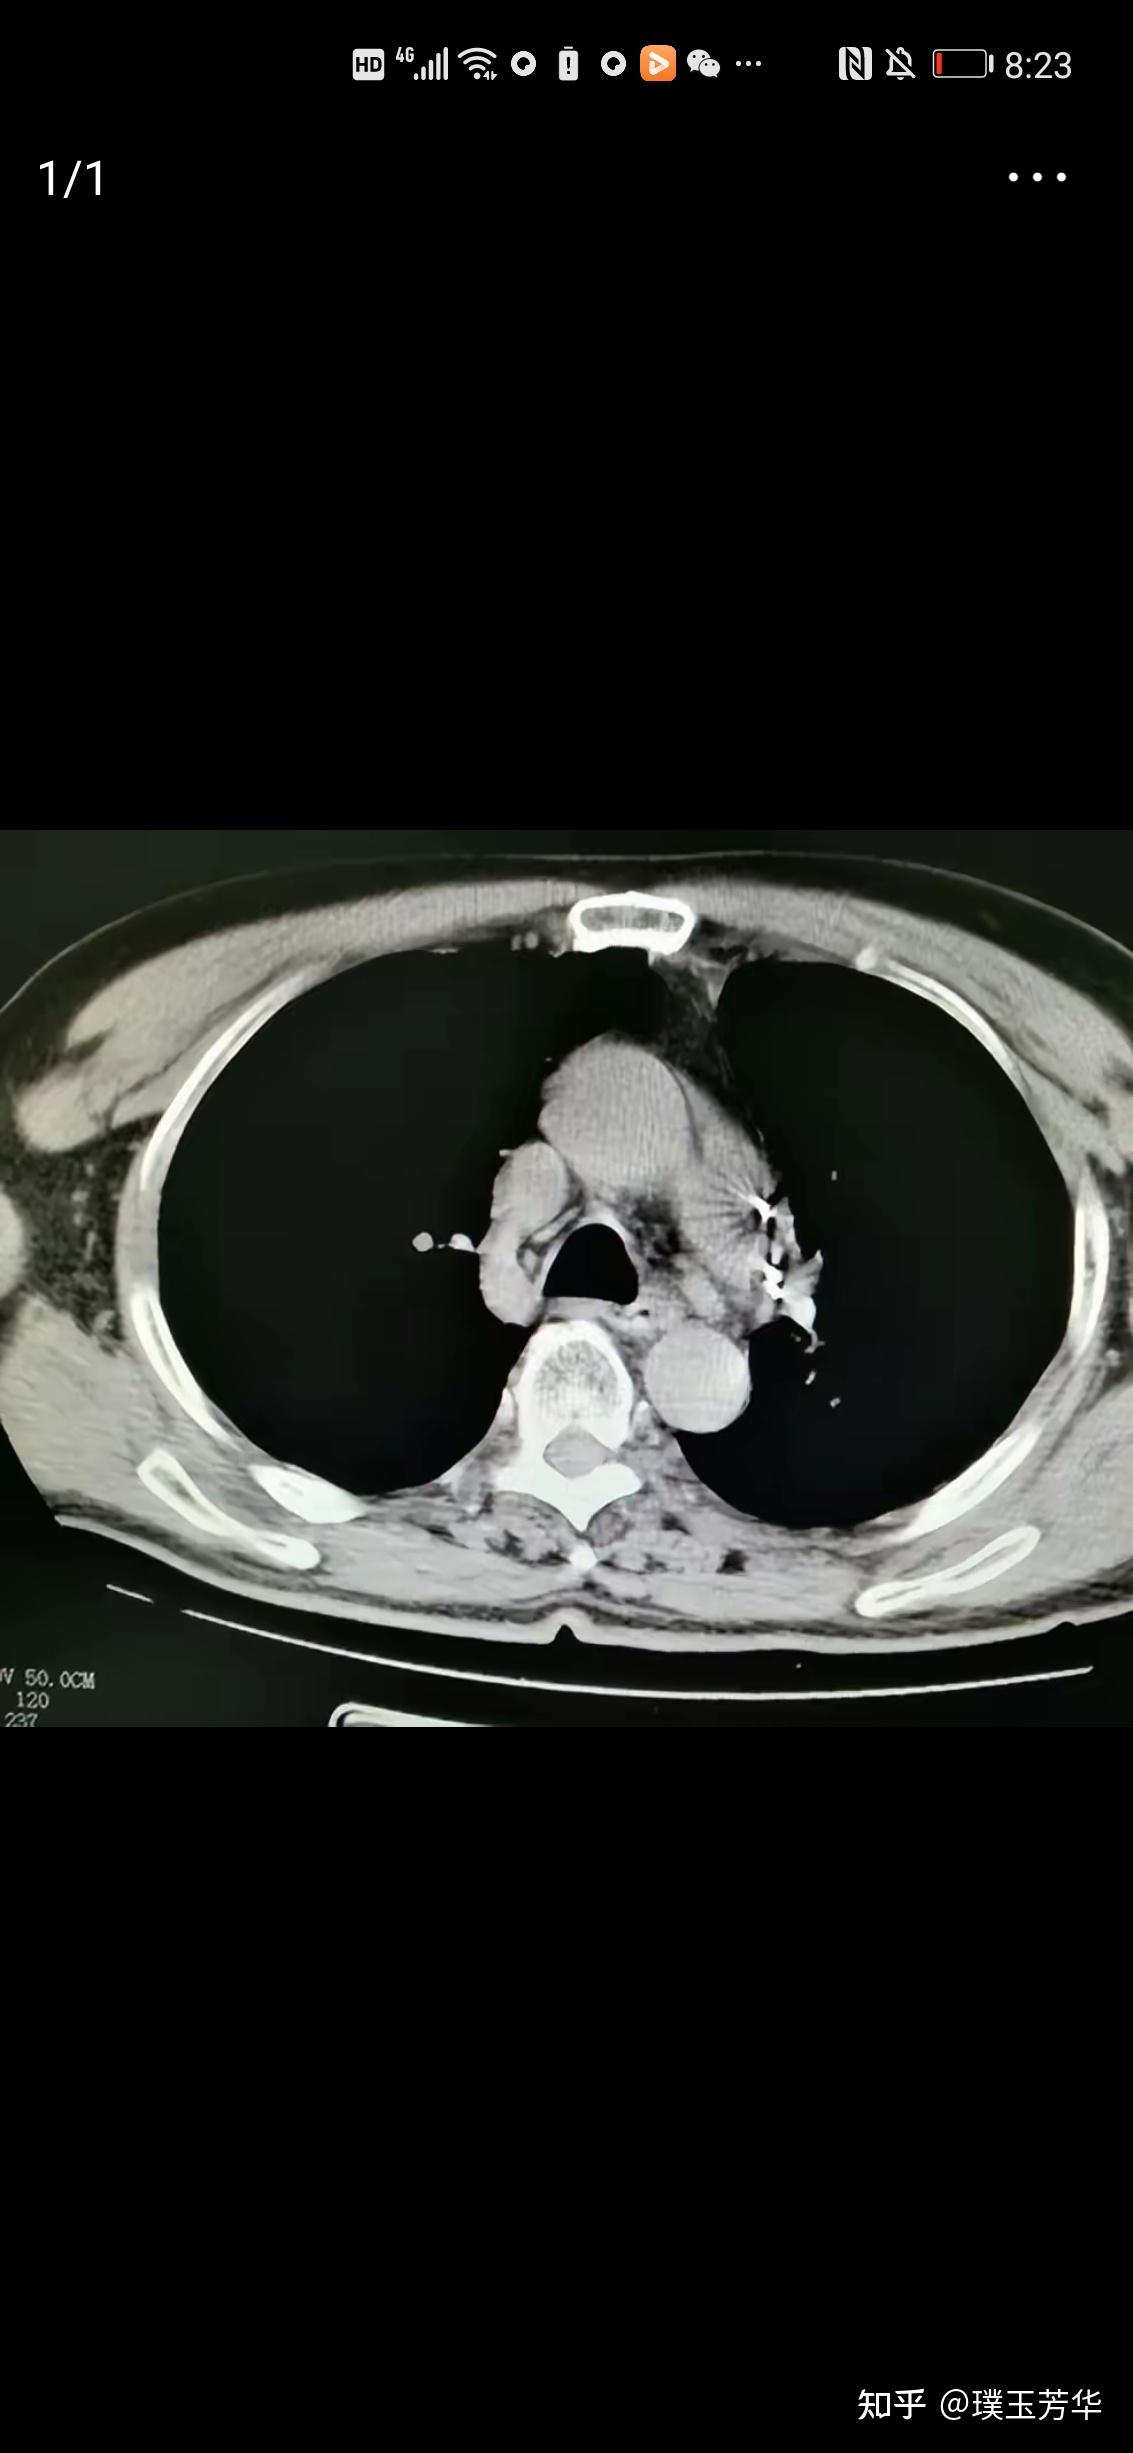

8厘米肺癌,4枚淋巴结转移 这位女士50多岁,不抽烟, 因为胸疼做ct检查